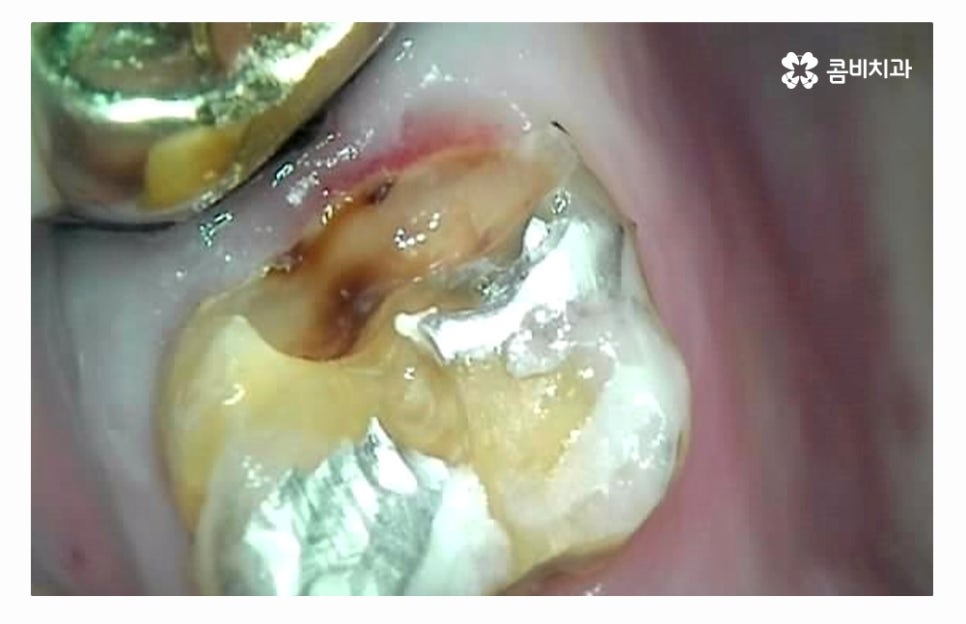

충치 치료 후에 시간이 지날수록 치아가 마모되거나

치료에 쓰인 재료의 수명이 다하는 경우도 생길 수 있기 때문에

치료 후 끝이 아니라 주기적인 검진과 스케일링이

항상 필수로 강조되고 있어요.